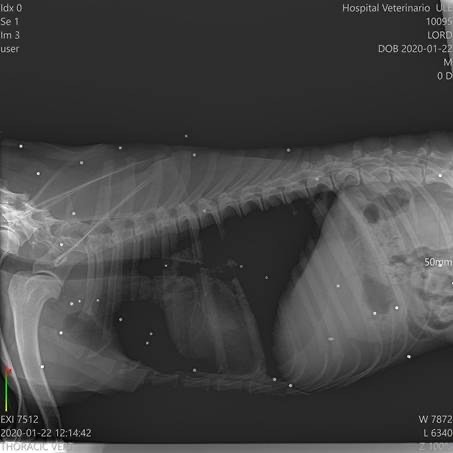

Der kleine Kerl begann zu humpeln und nach weiteren Untersuchungen sowie dem Besuch bei einem Spezialisten, wurde festgestellt, dass er unzählige Schrotkugeln im Körper hat und Arthrose in diversen Gelenken.Lord wird leider zukünftig auf Schmerzmedikamente angewiesen sein.

Der kleine Kerl begann zu humpeln und nach weiteren Untersuchungen sowie dem Besuch bei einem Spezialisten, wurde festgestellt, dass er unzählige Schrotkugeln im Körper hat und Arthrose in diversen Gelenken.